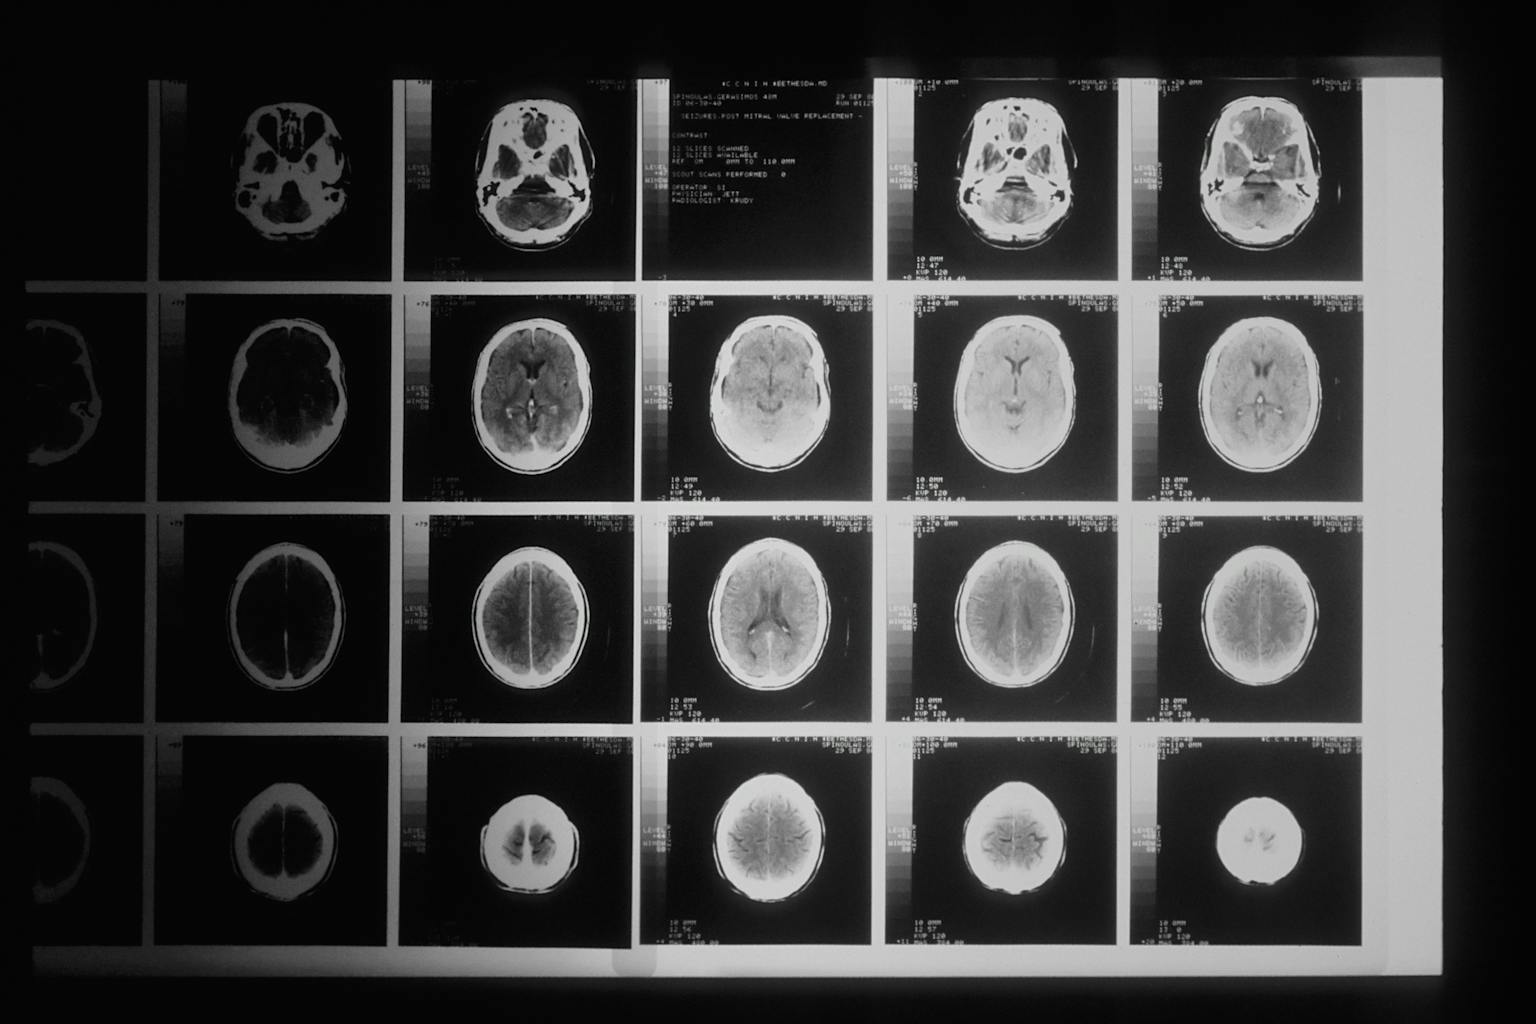

El mayor estudio de su campo ha demostrado relación entre la formación musical y el desarrollo cerebral. El estudio, publicado en el Journal of the American Academy of Child & Adolescent Psychiatry, analizó escáneres cerebrales de 232 niños de entre 6 y 18 años. Los investigadores han encontrado evidencias que sugieren que tocar música altera las zonas motoras y de regulación del comportamiento del cerebro.

Estudios anteriores habían demostrado una correlación entre el engrosamiento y adelgazamiento de zonas específicas del córtex cerebral y problemas de salud mental en niños, como ansiedad, depresión y déficit de atención.

En este nuevo estudio, se descubrió que la práctica musical influye el engrosamiento de la zona del córtex asociada con “las funciones ejecutivas, incluida la memoria de trabajo y el control atencional, así como la organización y la planificación para el futuro”.